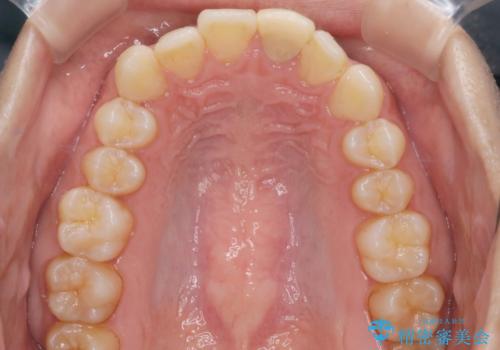

- 前歯のがたつきと口元を下げたいとのことで来院されました。

骨格的に左右差があるので正中を合わせることと抜歯矯正での口元改善は難しいことを説明させていただきました。

患者様に理解していただいた上で、インビザラインにてIPR(歯と歯の間を削る処置)を行いながら前歯のがたつきを整える治療計画を立てました。